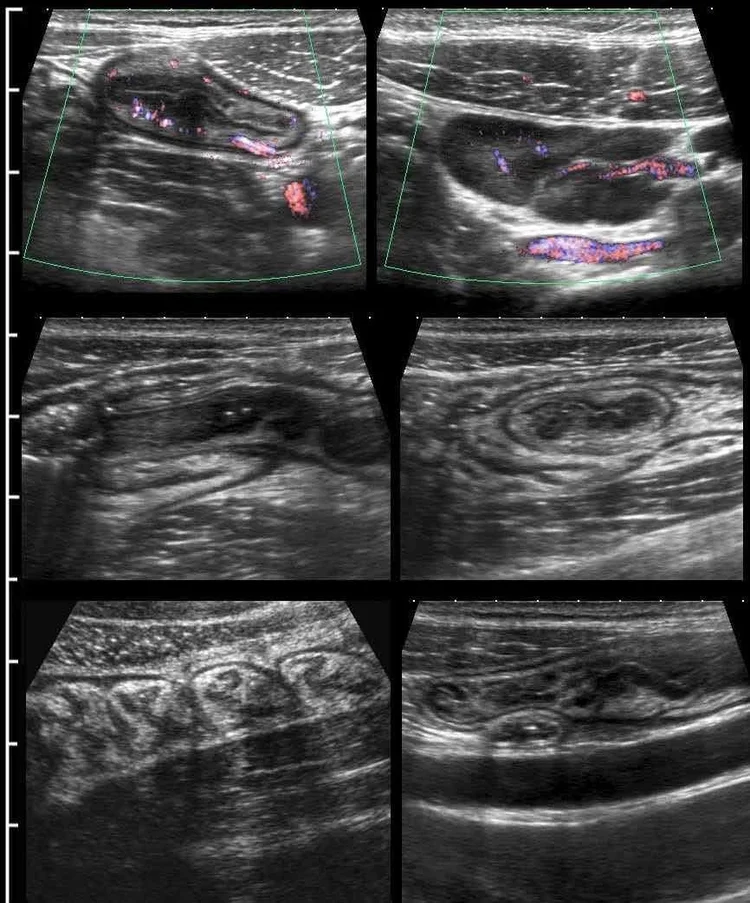

IUS is a type of abdominal ultrasound performed by specially qualified Gastroenterologists who are trained to identify abnormalities in the intestinal wall. It is used to assess and diagnose conditions of the bowel such as Inflammatory Bowel Disease (IBD), constipation, bloating, Crohn’s Disease, Diverticulitis and Ulcerative Colitis.

IUS uses the same equipment as regular abdominal ultrasound however it is performed by specially qualified Gastroenterologists who are trained to identify abnormalities in the intestinal wall. Results are delivered in real-time. There is no radiation involved.

During the procedure, gel is applied to your abdomen to help the transducer move smoothly over your skin. This bounces soundwaves off the organs to visualise the small and large bowel via images on a screen.